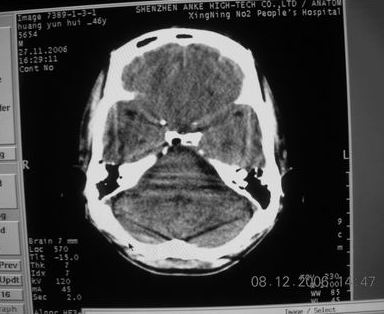

标题: CT11164:男,46岁,白血病患者,,大家看看. [打印本页]

标题: CT11164:男,46岁,白血病患者,,大家看看.

以前的片子,病史忘了,男,46岁,白血病患者,后来到中山二院诊断为

谁见过白血病中枢系统改变是怎么样的吗?

多发性脑脓肿?

白血病脑浸润。

支持白血病脑浸润.

1 多发脑脓肿可能性大.>2 白血病浸润.

白血病脑浸润。没见过!但结合病史应首先考虑此病。

支持白血病脑浸润

结合病史考虑白血病脑浸润。

结合白血病病史,支持考虑白血病脑浸润。

结合病史考虑白血病脑浸润